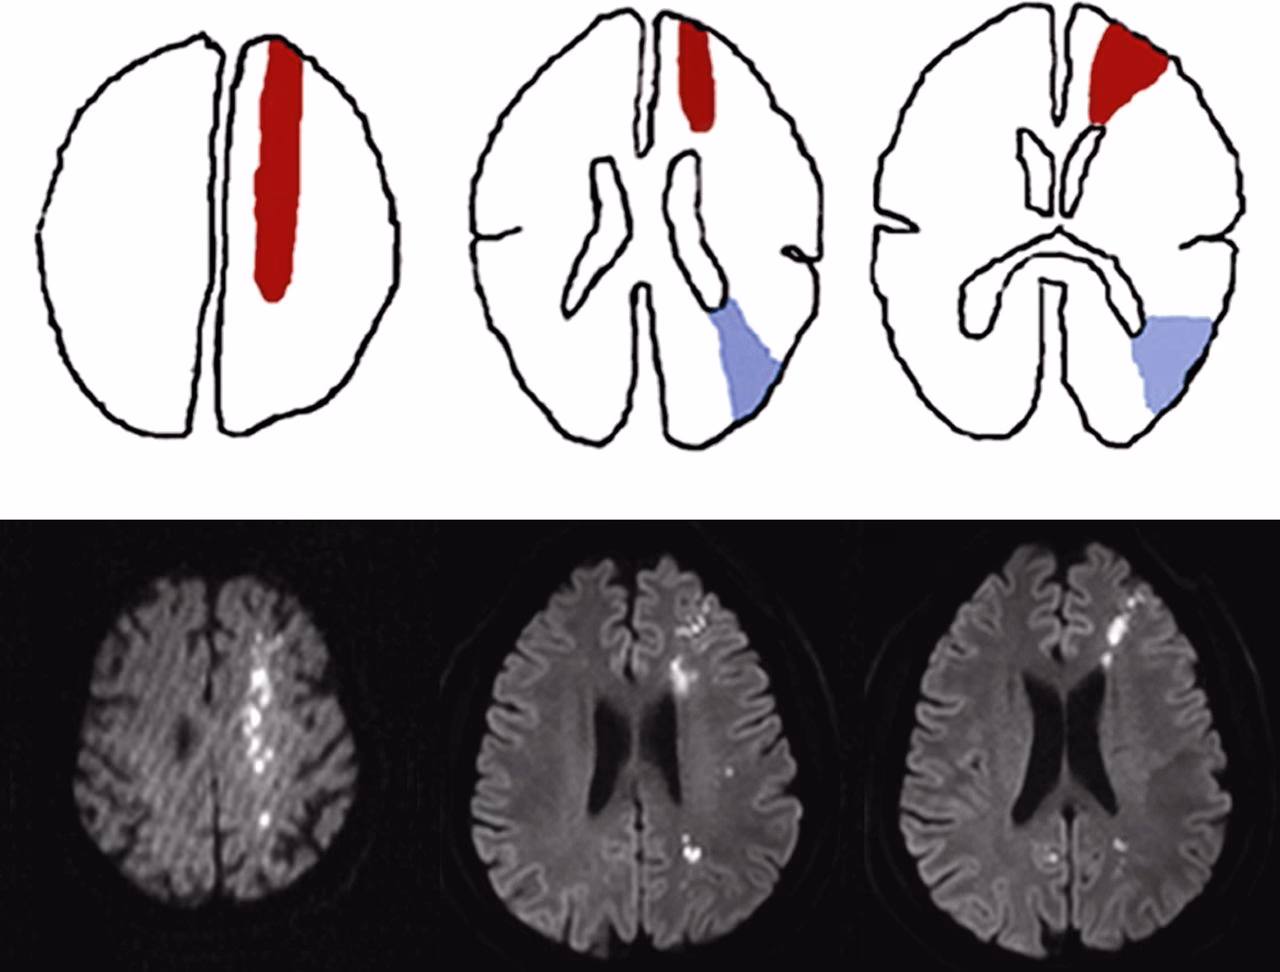

Aunque el concepto general es el mismo (lesión en la unión de territorios arteriales), se describen dos tipos principales de infartos de zona fronteriza supratentorial, basados en su localización anatómica dentro del cerebro:

Infartos de Zona Fronteriza Externos (Corticales o Superficiales)

Estos infartos se localizan en la corteza cerebral y la sustancia blanca subyacente, en la frontera entre los territorios de irrigación de la arteria cerebral media (ACM) y, por un lado, la arteria cerebral anterior (ACA), y por otro lado, la arteria cerebral posterior (ACP). Son lesiones que típicamente se ven en la periferia del cerebro, en la interfaz entre estos grandes territorios corticales.

Infartos de Zona Fronteriza Internos (Subcorticales o Profundos)

Estos infartos se encuentran más profundamente dentro del cerebro, en la sustancia blanca, específicamente en la interfaz entre las ramas perforantes profundas de la arteria cerebral media y el sistema arterial superficial (ramas corticales) de la misma ACM u otras arterias principales. A menudo se localizan alrededor de los ganglios basales o en el centro semioval.

El Diagnóstico de los infartos de zona fronteriza se realiza principalmente mediante neuroimagen, específicamente la resonancia magnética (RM) cerebral. Las secuencias de difusión (DWI) y el mapa de coeficiente de difusión aparente (ADC) son cruciales para identificar las lesiones isquémicas agudas en las ubicaciones típicas de zona fronteriza.